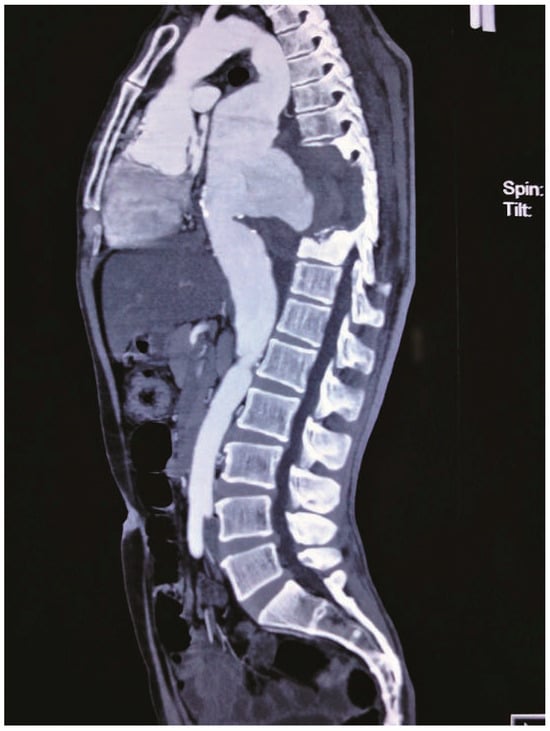

Case report. A 63-year-old hypertensive male presented with atypical chest discomfort and breathlessness on exertion [...]